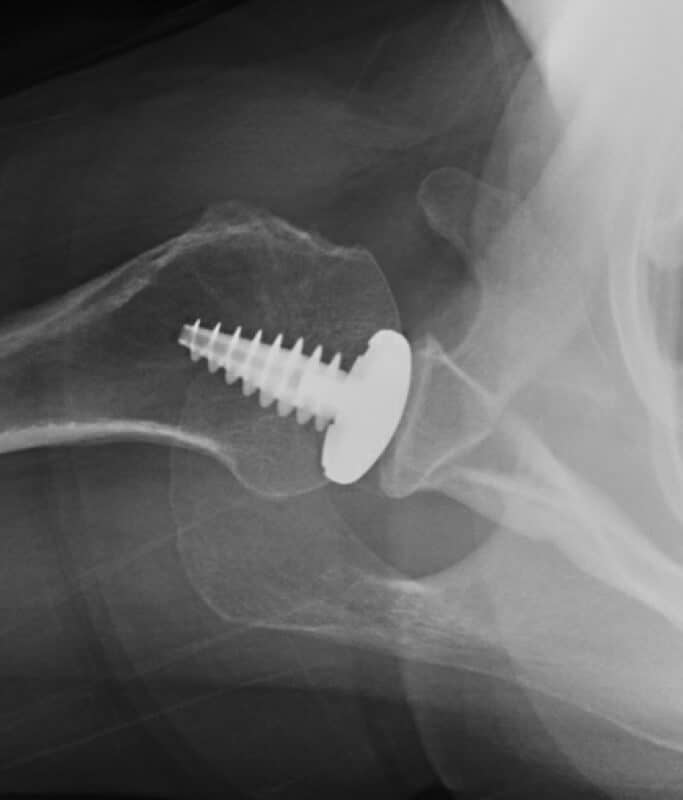

Arthrosurface, HemiCap Small